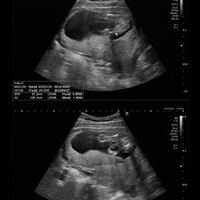

妊娠16週で、早くも性別がわかったので、エコー画像をまじえて報告いたします( ´ ` )ノ 妊娠16週で性別がわかるとは思ってなかったので、とっても嬉しい! お医者さんに聞いたところ、条件がととのえば妊娠16週で性別がわかるんですって。 妊娠24週ってどんな時期?! エコーで赤ちゃんの性別が確定できました♡女の子の場合でも断定できる!葉っぱマークや子宮が見えるって本当?? そしてツワリも終わって気をつけたいのが体重管理!! 妊娠中の体重増加の目安って?ツワリで減った場合は、どの時点の体重から考える

エコー 性別 女の子 子宮- それに比べて三男は性別が二転三転して30週くらいまで確定しませんでした。 私も性別が確定するまでネットでエコー写真をたくさん見ていたので(笑) 参考になればと思い(ならないんですけどね笑) ブログにまとめてみました。 妊娠23週で女の子に性別が変わった!!エコー写真あり そして妊娠6ヶ月、23週1日目に性別が覆ったエコー写真がこちら! 矢印の先に黒い一本の線があるの分かりますか? これが女の子の割れ目だそうです! 先生から 「結果女の子だったね~!女の子で

妊娠5ヶ月(16・17・18・19週) 赤ちゃんの性別がはっきりしてくるため、早ければエコー写真に外性器が写ることがあります。 手足を動かすこともあり、人によっては胎動を感じ始める時期です。 赤ちゃんの身長は約25cm、体重は約250gになります。 メロン